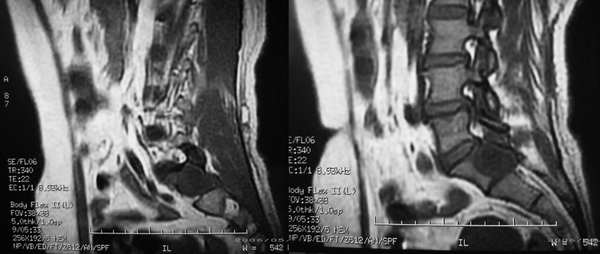

患者,女性,60岁。腰痛、腿痛一周余,临床医生考虑:椎间盘突出,行ct及mr检查

病灶为长t1长t2信号,对s1椎体是压迫吸收,应首先考虑骶管囊肿。建议增强扫描。

征象:1、骶椎管偏右侧囊性病变,长t1长t2改变,均匀。2、慢性病变过程,邻近骨质有吸收变薄。

考虑:盲囊蛛网膜囊肿。

S1椎长T1长T2信号,与蛛网膜下腔相连,边界清晰,CT可见局部骨质吸收,边缘硬化改变。支持骶管囊肿。